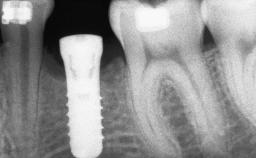

Guided Bone Regeneration (GBR) with a Particulated Autologous Graft and a ePTFE-Reinforced Membrane for Vertical Augmentation of a Single-Tooth Edentulous Space in the Esthetic Zone

A 47-year-old Caucasian woman with a single-tooth edentulous space at the site of the left maxillary canine was referred for treatment. She had undergone traumatic extraction of this impacted canine several months before referral. Her chief complaint was the dissatisfying appearance of her smile. The patient desired a stable and esthetic rehabilitation of the site. Her dental history showed no evidence of periodontal disease or bruxism. She had no systemic diseases, was not taking any medications, and did not smoke. The extraoral examination revealed a high lip line and an inadequate soft-tissue volume at the defective canine site. Large black triangles were visible between the canine and its adjacent teeth.